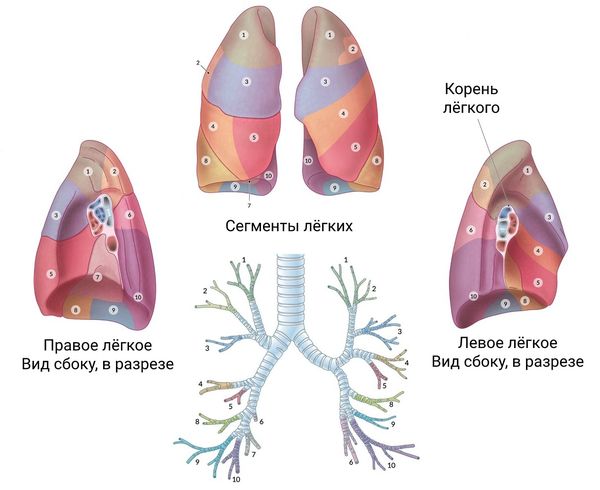

Анатомические изображения сегментов легких различных животных

Раздел: Другие животные